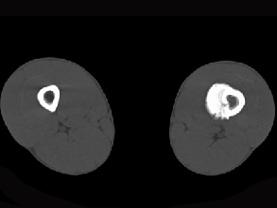

问题 患者,男,23岁,左大腿远端疼痛,夜间明显,服阿司匹林可缓解,请结合所提供图像,选择最佳答案 ( )

选项 A、骨巨细胞瘤 B、骨肉瘤 C、骨样骨瘤 D、骨化性纤维瘤 E、骨脓肿

答案 C